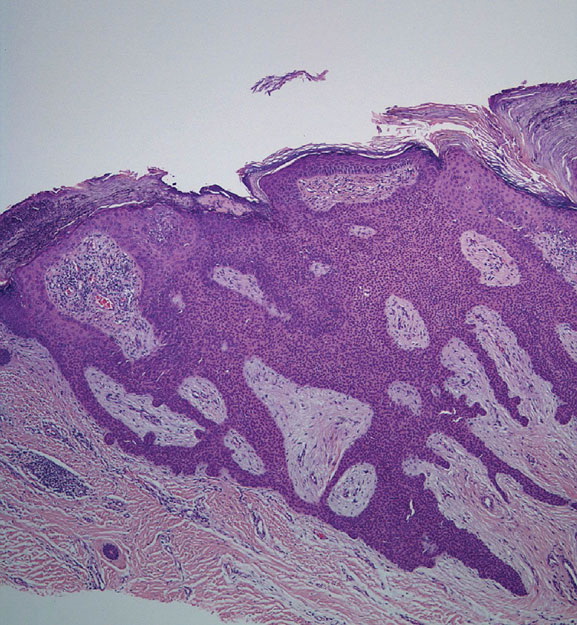

Hidroacanthoma simplex shows sharply demarcated aggregations of cuboid to ovoid cells confined to the epidermis. Eccrine poroma reveals aggregations of uniform basaloid cells that radiate from the basal layer of the epidermis into the dermis . Dermal duct tumor consists of several sharply circumscribed, mainly dermal nodules composed of poroid and cuticular cells. Ductal structures are frequently observed. Poroid hidradenoma is characterized by intradermal, solid, and cystic aggregations of poroid cells.